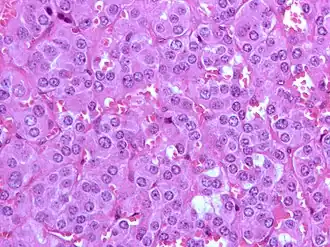

Un phéochromocytome est une affection tumorale parfois maligne. Cette tumeur se développe à partir des cellules chromaffines de la médullo-surrénale. Ne pas confondre avec le corticosurrénalome (en) qui, quant à lui, se développe à partir du cortex de la glande surrénale. Celui-ci se manifeste par une hypertension artérielle grave.

Il doit être évoqué devant les symptômes, l'imagerie retrouve une masse surrénalienne. Dans 10 % des cas on retrouve une masse extra-surrénalienne, on parle alors de paragangliome. Le diagnostic définitif est anatomo-pathologique.